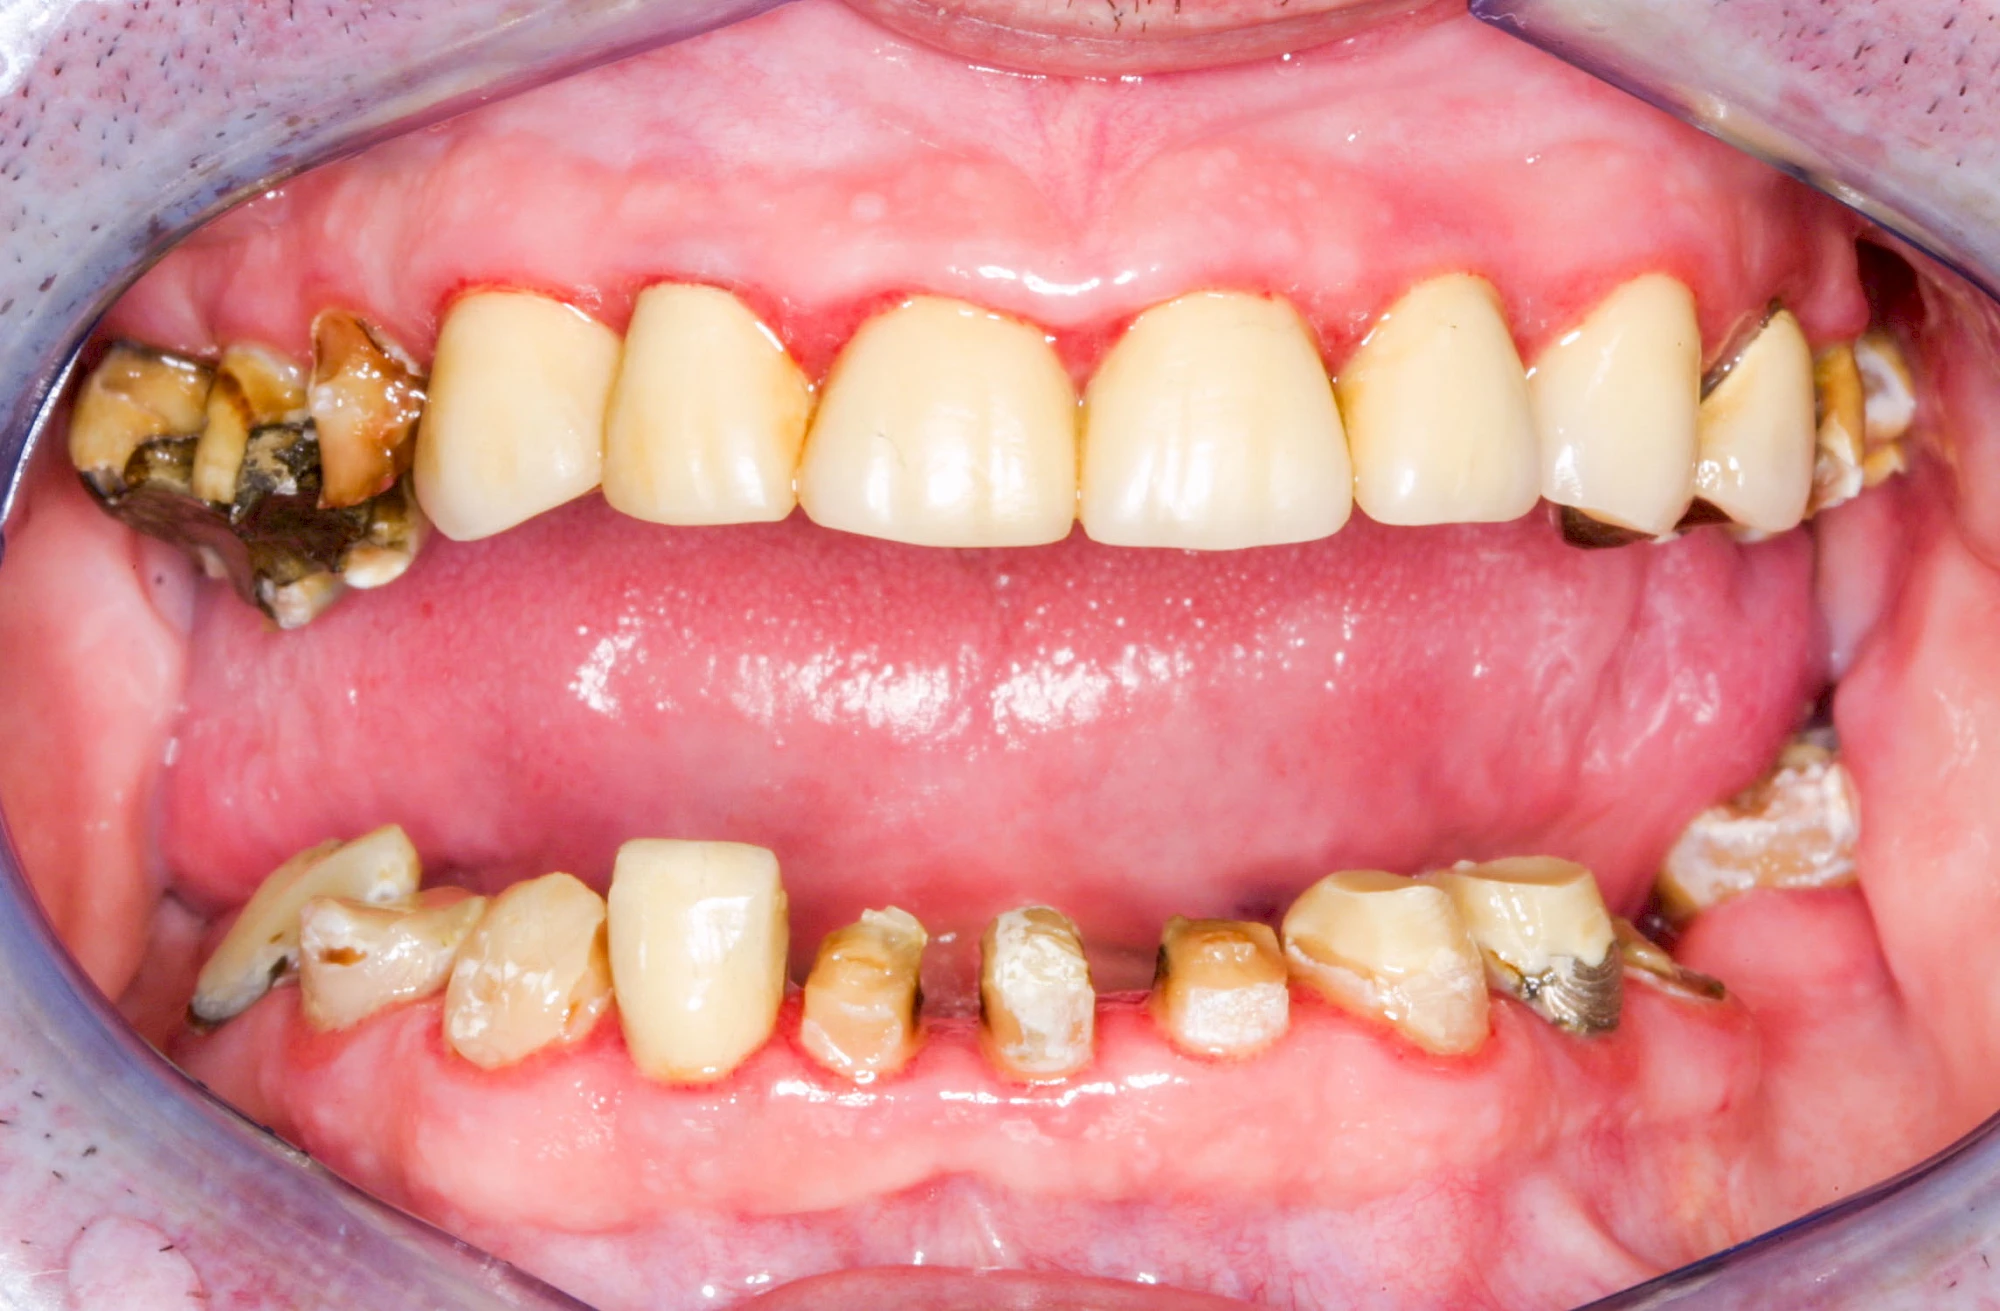

Ist zunächst nur das Zahnfleisch von der Entzündung betroffen, spricht man von Gingivitis. Später, wenn auch der Knochen um die Zähne herum entzündet ist, spricht man von einer Parodontitis. Bei der Parodontitis wird der Knochen nach und nach abgebaut und das Zahnfleisch zieht sich zurück. Die Zahnhälse und Zahnwurzeloberflächen liegen mehr und mehr frei. Die Zähne werden zunehmend lockerer und fallen schließlich aus.